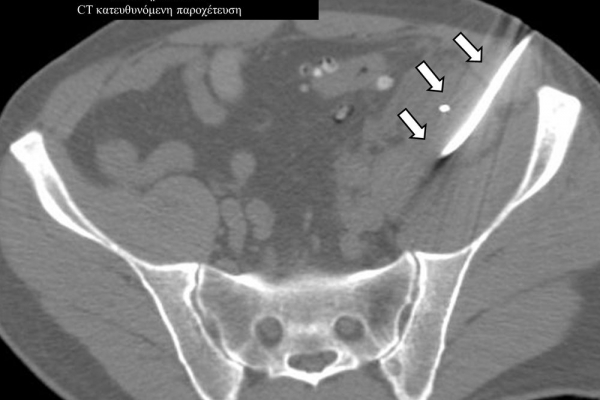

Η παρέμβαση διενεργείται υπό την καθοδήγηση αξονικού τομογράφου ή υπερήχων ή και με συνδυασμό τους. Ο επεμβατικός ακτινολόγος αρχικά αναισθητοποιεί την ανατομική περιοχή ενδιαφέροντος με τη χρήση τοπικής αναισθησίας και παρακεντεί την συλλογή διαδερμικά με λεπτή βελόνη. Στη συνέχεια μέσω ομοαξονικών συστημάτων συρμάτων-καθετήρων-διαστολέωντοποθετείται διαδερμικός καθετήρας τύπου pig-tail εντός της συλλογής, ο οποίος συνδέεται με εξωτερική παροχέτευση.